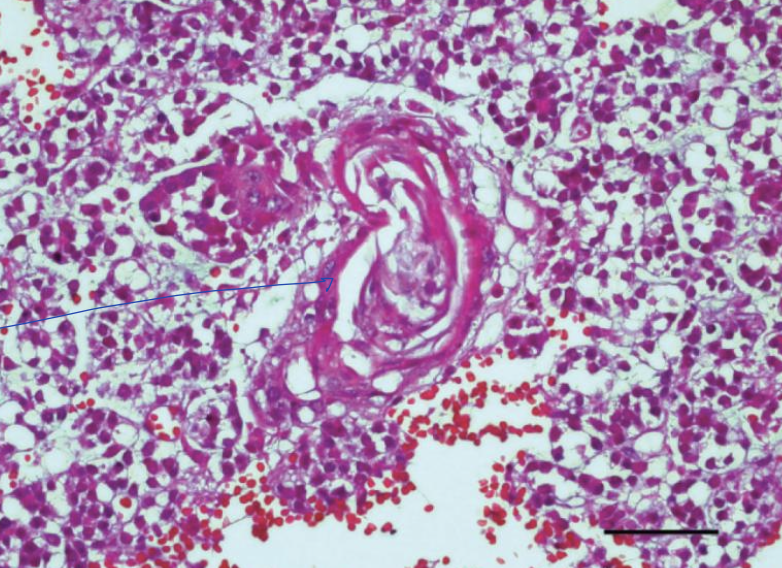

what is the image showing?

sialoliths